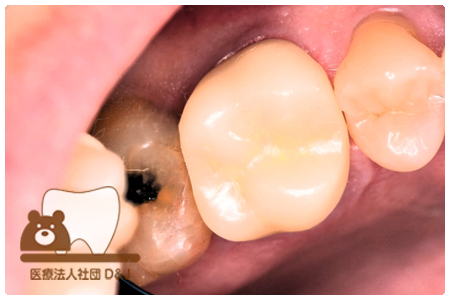

症例3フリジルコニアクラウン 左上6

治療前

治療後

59歳 男性

- 治療内容

- 虫歯で大きく失われた歯に対して、土台としてファイバーコアを使用し、その上にフルジルコニア製の被せ物を装着しました。見た目と強度を両立した自由診療の治療です。

- 治療期間

- 根の治療含めて3カ月半

- 費用

- 自費

フリジルコニアクラウン:77,000円(税込)

(R8.2月時点)

- その他の治療の費用は含まれておりません。

- リスク・副作用

- 強い力が加わると割れる可能性があります。また、噛み合わせや歯ぎしりの影響で脱離することがあります。